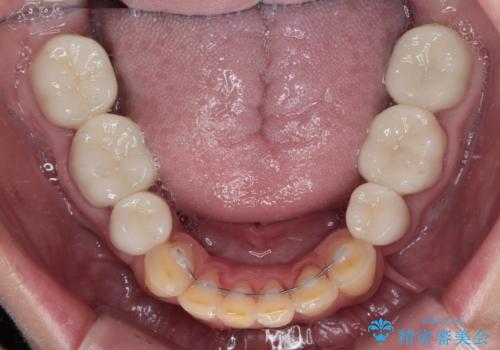

矯正治療終了後に、残った歯をオールセラミッククラウンにて補綴治療を行うこととしました。

途中来院が困難な時期があったり、歯周外科処置を行って治癒を待ったりと、治療期間は長くなりましたが、初診時とは比べものにならないくらいきれいに仕上げることができました。